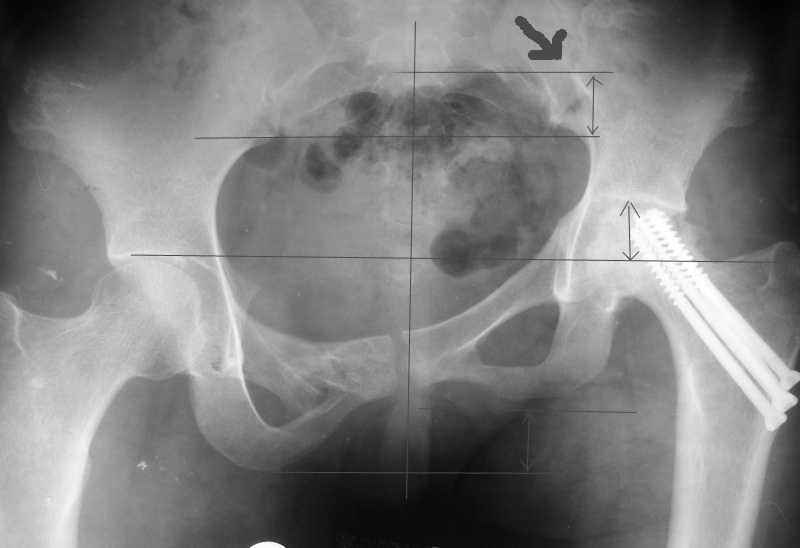

Re: AVN of femoral head and fracture of the pelvis.

Привет, Макс. Не торопись, посмотри внимательно на истинную картину. Толстая стрелка указывает на нижний край смещенного кп сочленения.

Поэтому считаю, что Принять какое-либо решение без кт и дополнительных проекций неразумно.